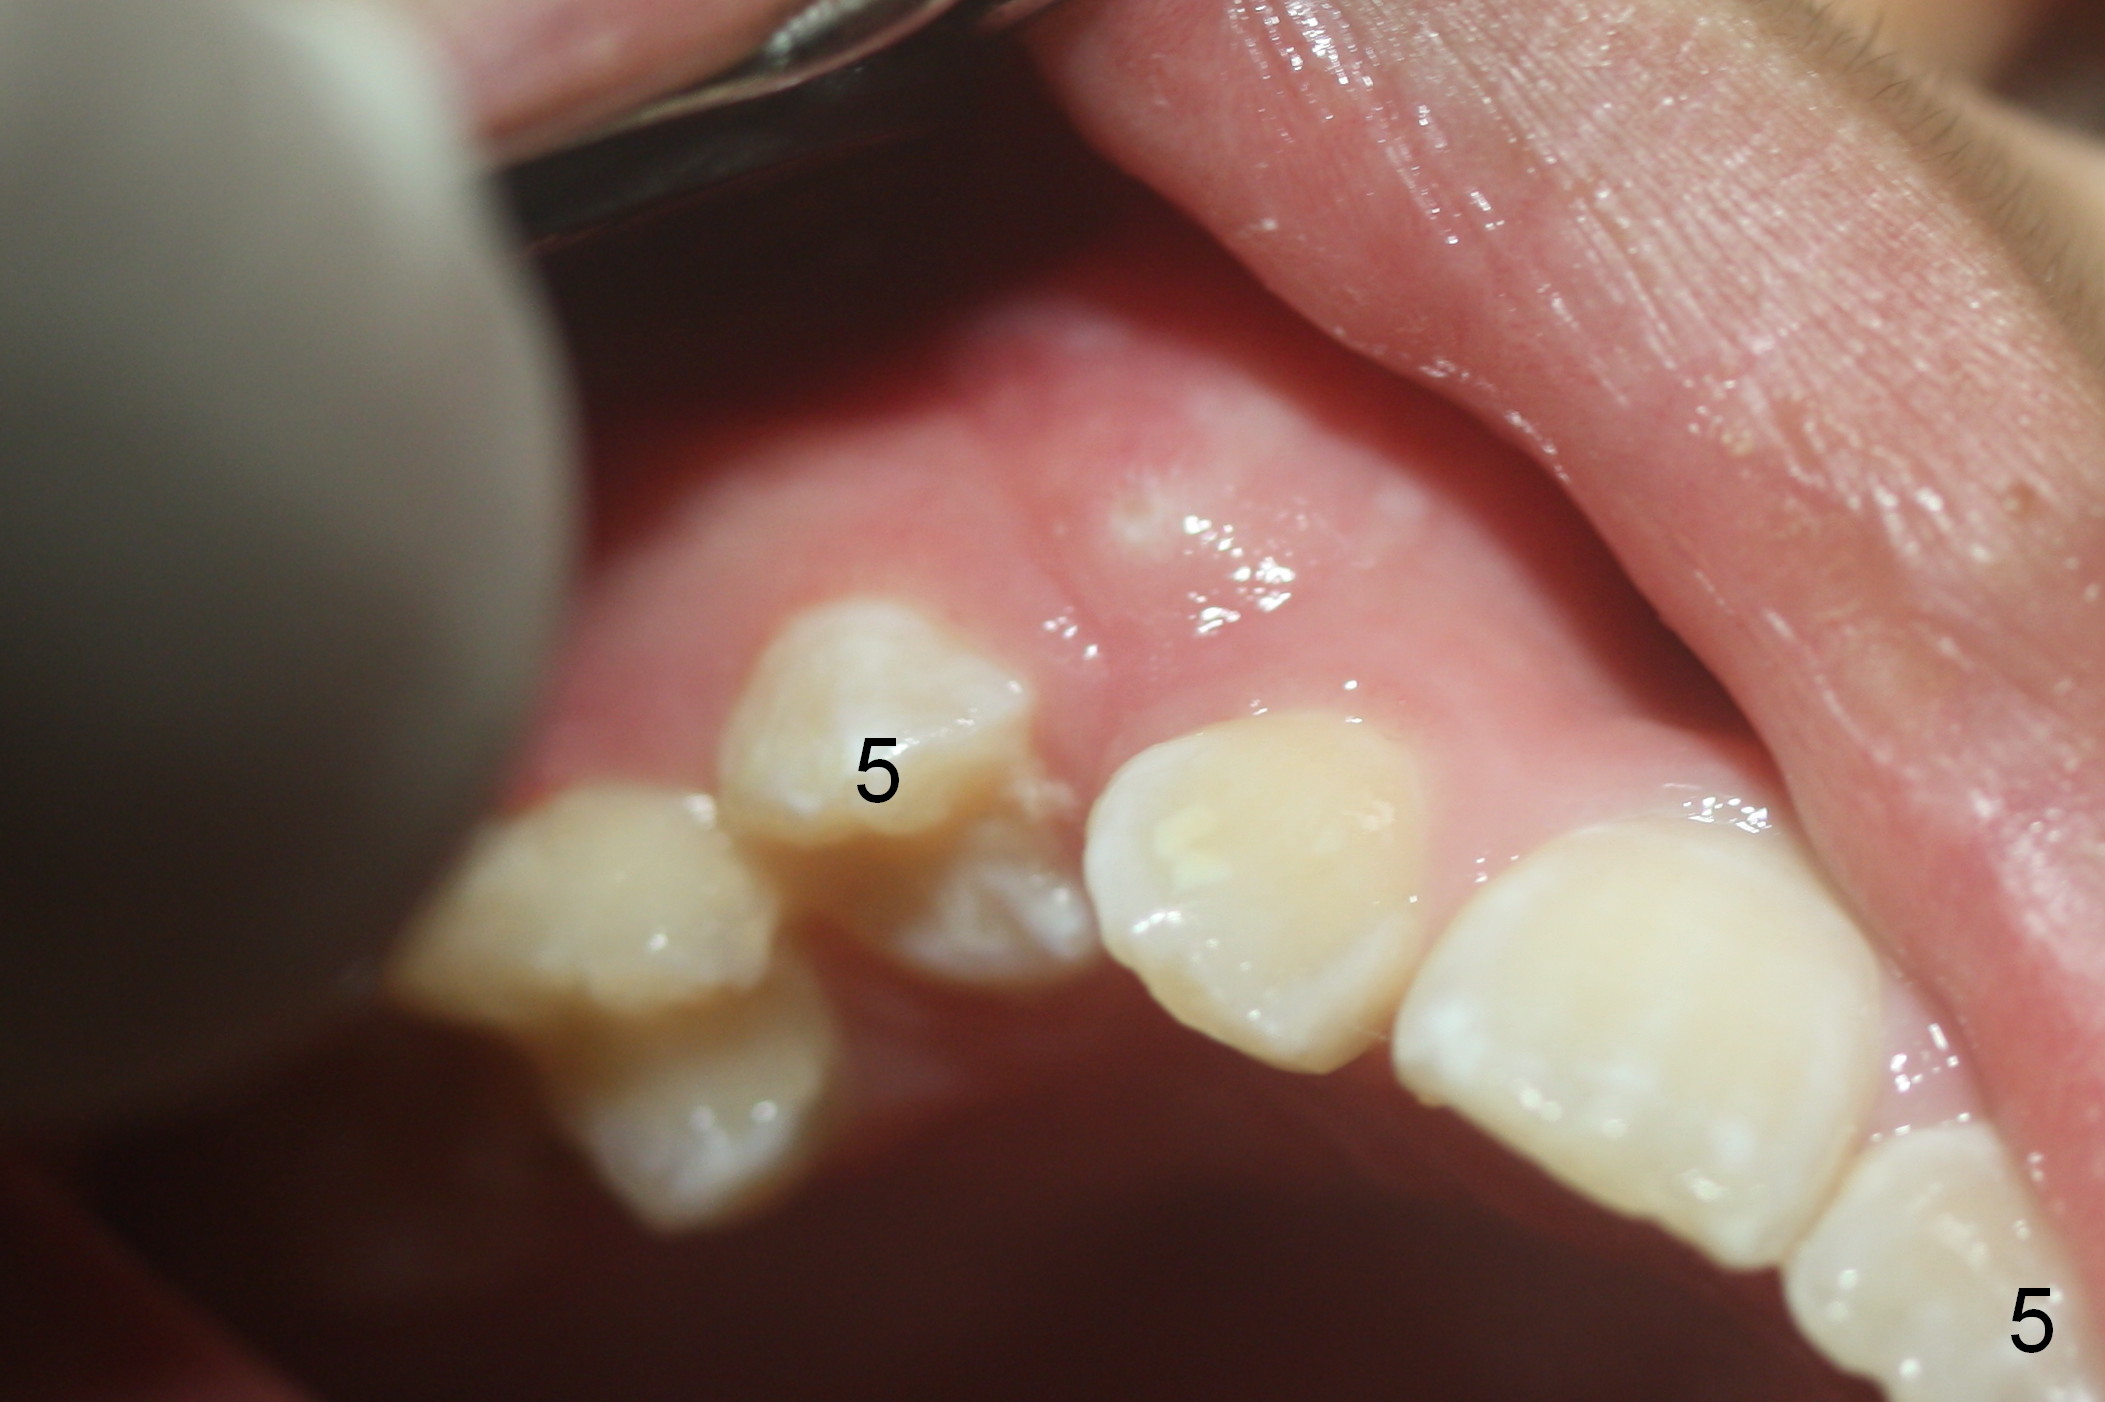

One month later, the tooth #5 erupts more (Fig.5,6) and is extracted (Fig.8-10). The tooth S is to be extracted to make room for #27 and 28 eruption (Fig.7).

Another 1 month, the teeth #4 and 6 are erupting (Fig.11,12). The tooth A is to be extracted. It is assumed that the diastema between #7 and 8 (due to #7 mesial shift in turn due to #6 erupting, Fig.11 arrow (as compared to Fig.6 <)) will be closed once the tooth #6 erupts fully.